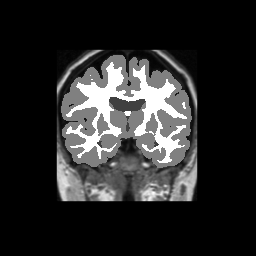

Accuracy is reported as Dice overlaps between a tool's segmentation and the Internet Brain Segmentation Repository (IBSR) manual segmentation for each of the 18 IBSR subjects. The inter-tool comparison (on the left below) shows the median Dice coefficient for each tissue class. The overlaps for FSL (from which the median values are drawn) are shown in the plot on the right.

Subject Accuracy (IBSR)

Overlap coefficients for each tissue class are shown here for each IBSR subject. Select a subject below to see the FSL results compared to other tools.